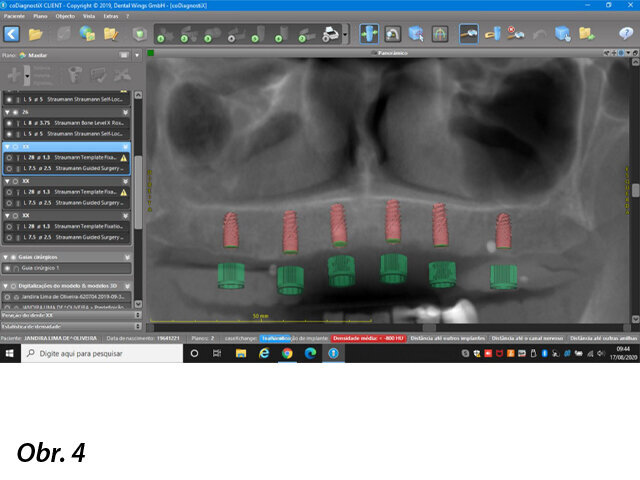

Pacientka se dostavila na naši kliniku se snímatelnou náhradou v horní čelisti (obr. 1), která vykazovala nízkou stabilitu a nevyhovující žvýkací funkci. Pacientka si stěžovala i na estetiku, ale funkční aspekt byl pro ni rozhodující. Po klinickém vyšetření (obr. 2–3) a CBCT analýze jsme naplánovali zavedení šesti implantátů Straumann BLX jako oporu pro fixní můstek v rozsahu celého oblouku (obr. 4). Provizorní můstek byl vyroben před zavedením implantátů. K provedení statické řízené operace byla vytištěna chirurgická šablona.